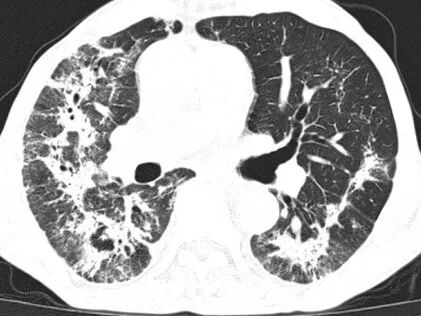

然而,病情的凶险程度远超预期,检查结果提示D-二聚体显著升高,CTPA提示右下肺动脉肺栓塞,肺部感染亦较前明显进展,病情进一步恶化。在呼吸与危重症医学科主任李芳芳带领下,团队迅速调整方案,加强抗凝与抗炎治疗。

胸部CT及CTPA